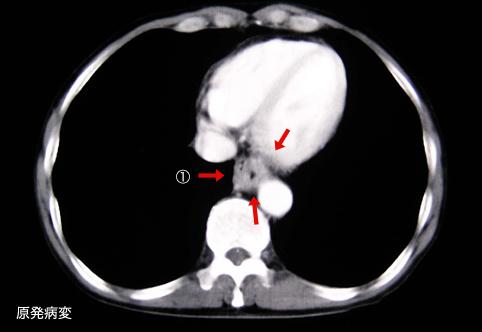

질환(병리주체)의 분류 악성 상피성종양/편평상피암

부위(장기별) 식도/하

검사방법 CT

종양의 육안분류 3형(궤양침윤형)/

종양의 최대경(밀리미터) 35~40

종양의 심달도 s(a)